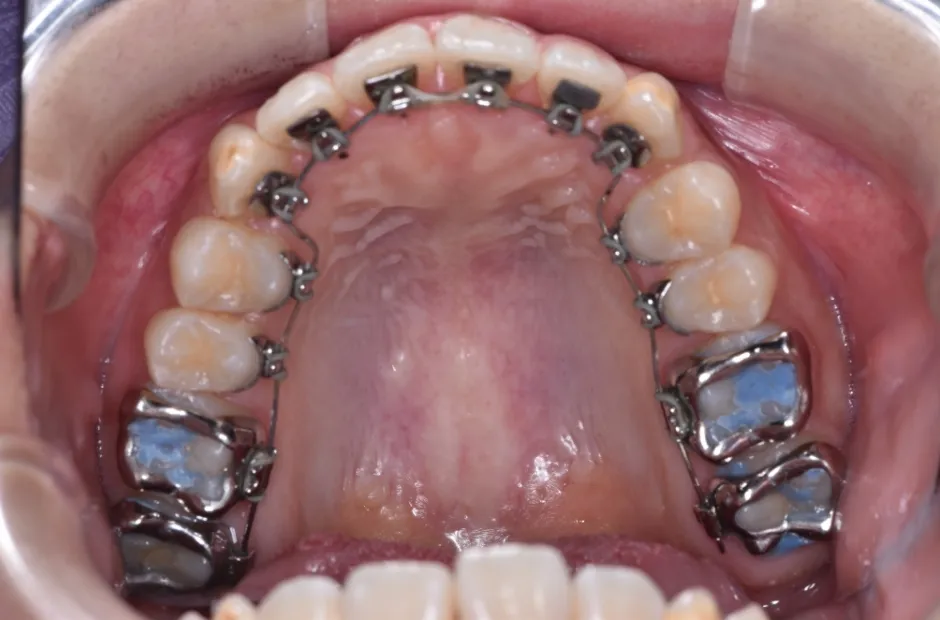

叢生

| 診断名・主訴 | 叢生 |

|---|---|

| 年齢・性別 | 43歳・女性 |

| 治療期間・回数 | 2年7か月 27回 |

| 治療に用いた主な装置 | 舌側矯正 |

| 抜歯部位 | 両顎4,4 |

| 治療費 | 100万円(税抜) |

| リスク・副作用 | 装置による違和感・疼痛・歯肉退縮・歯根吸収・虫歯のリスクなど |

治療前

治療中

治療後